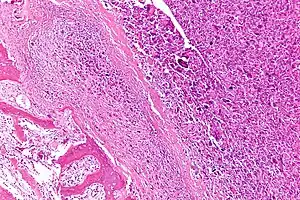

| Intermediate-magnification micrograph of an osteosarcoma (center and right of image) adjacent to non-malignant bone (left-bottom of image): The top-right of the image has poorly differentiated tumor. Osteoid with a high density of malignant cells is seen between the non-malignant bone and poorly differentiated tumor (H&E stain). | |

Microscopically: The characteristic feature of osteosarcoma is presence of osteoid (bone formation) within the tumor. Tumor cells are very pleomorphic (anaplastic), some are giant, numerous atypical mitoses. These cells produce osteoid describing irregular trabeculae (amorphous, eosinophilic/pink) with or without central calcification (hematoxylinophilic/blue, granular)—tumor bone. Tumor cells are included in the osteoid matrix. Depending on the features of the tumor cells present (whether they resemble bone cells, cartilage cells, or fibroblast cells), the tumor can be subclassified. Osteosarcomas may exhibit multinucleated osteoclast-like giant cells.[22]